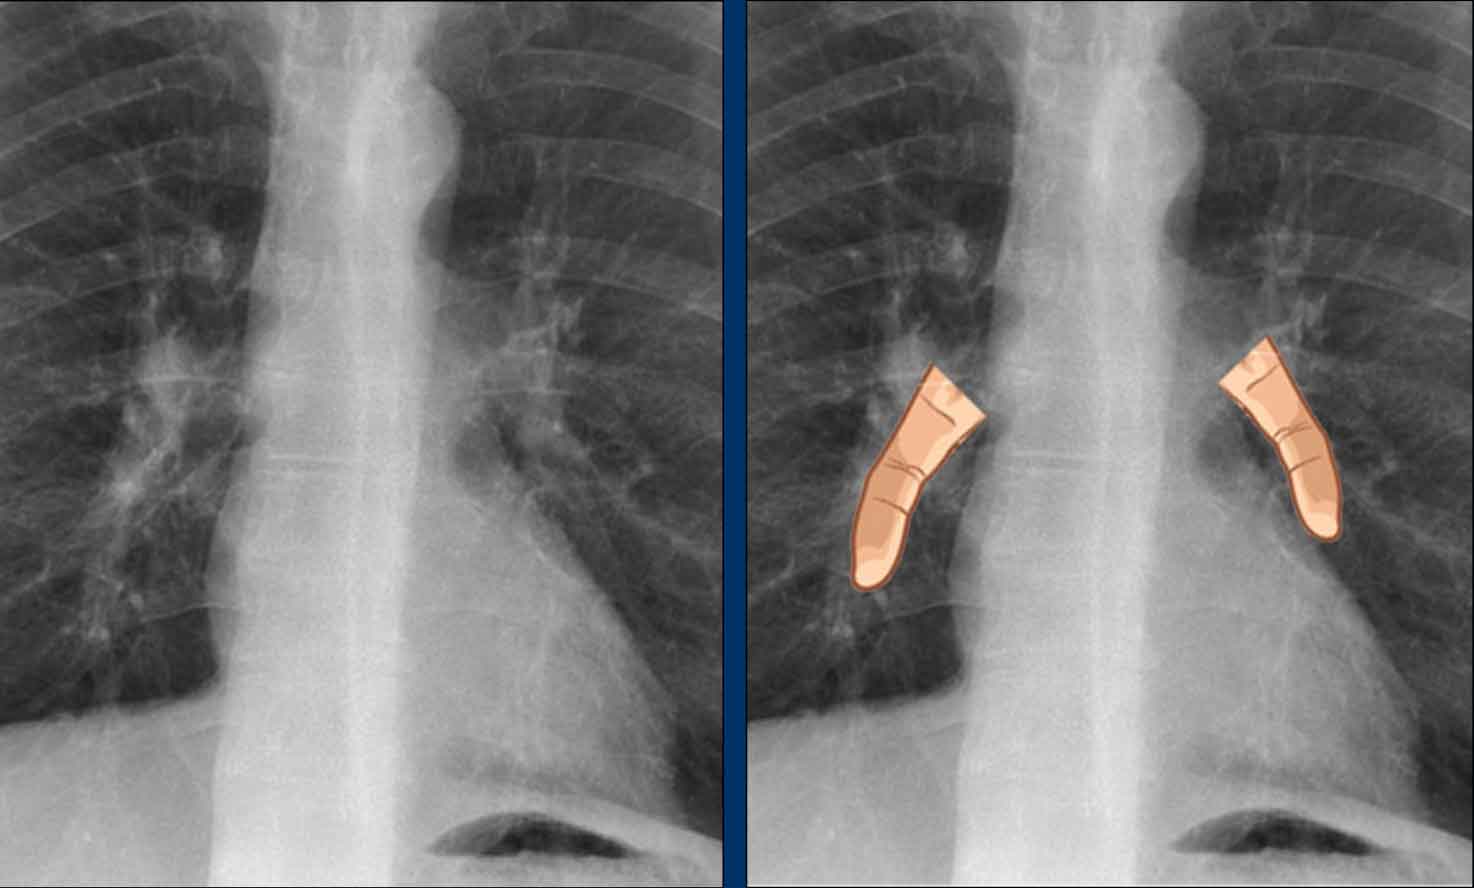

Valvular Anatomy on Lateral Radiograph

• To localize cardiac valves on lateral view, draw a line from the carina to the cardiac apex:

• Above the line: Aortic and pulmonic valves

• Below the line: Tricuspid and mitral valves (4)

This line helps to approximate valve locations and assess for chamber-specific enlargement.